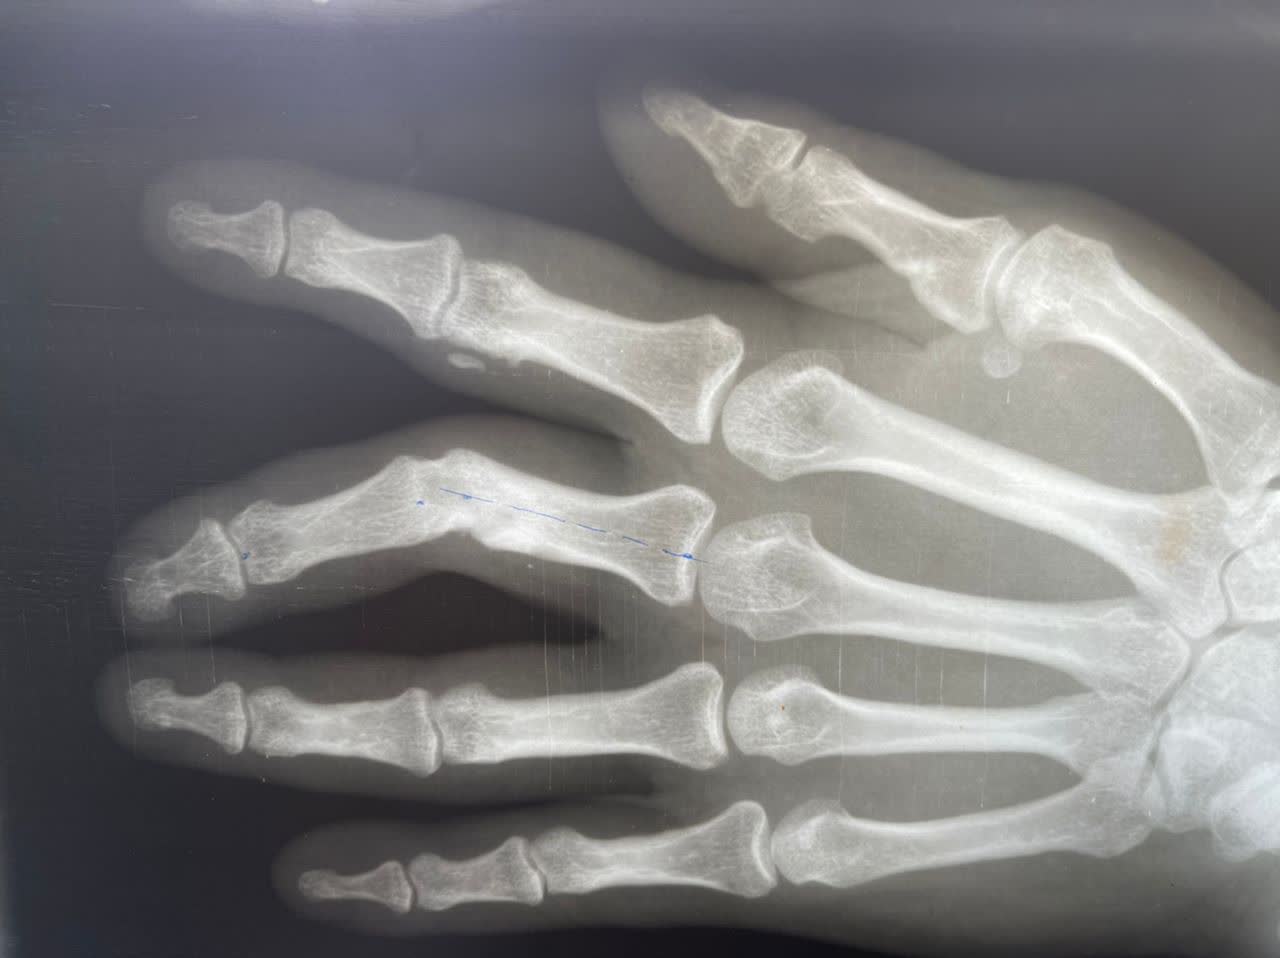

بنا به گزارش روابط عمومی بیمارستان قمربنی هاشم (ع) جوین:انجام عمل سنگین جراحی تعویض مفصل لگن (THA) در بیمار ،خانمی 65 ساله از اهالی شهرستان جوین به دنبال شکستگی گردن استخوان ران و عمل جراحی استئوتومی اصلاحی انگشت در بیمار ،آقایی 33 ساله از اهالی شهرستان جوین به دنبال آسیب قدیمی ، جهت اصلاح راستای انگشت در بیمارستان قمربنی هاشم (ع) جوین انجام شد.

گرافی قبل از جراحی                                                    گرافی پس از جراحی

قبل از عمل